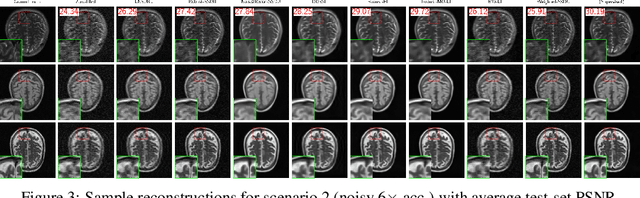

Abstract:Reconstructing MRI from highly undersampled measurements is crucial for accelerating medical imaging, but is challenging due to the ill-posedness of the inverse problem. While supervised deep learning approaches have shown remarkable success, they rely on fully-sampled ground truth data, which is often impractical or impossible to obtain. Recently, numerous self-supervised methods have emerged that do not require ground truth, however, the lack of systematic comparison and standard experimental setups have hindered research. We present the first comprehensive review of loss functions from all feedforward self-supervised methods and the first benchmark on accelerated MRI reconstruction without ground truth, showing that there is a wide range in performance across methods. In addition, we propose Multi-Operator Equivariant Imaging (MO-EI), a novel framework that builds on the imaging model considered in existing methods to outperform all state-of-the-art and approaches supervised performance. Finally, to facilitate reproducible benchmarking, we provide implementations of all methods in the DeepInverse library (https://deepinv.github.io) and easy-to-use demo code at https://andrewwango.github.io/deepinv-selfsup-fastmri.